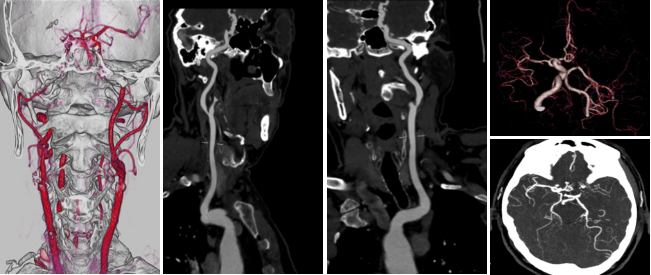

病例四 男,64歲, 頭暈胸悶查因。 執(zhí)行頭頸血管+心臟冠脈一站式低劑量掃描。

一次掃描 、一次打藥60ml完成頭頸心一站式掃描,各血管及小分支清晰可見(jiàn) , 頸 部 血管未見(jiàn)明顯異常, 冠脈有狹窄及多發(fā)斑塊。